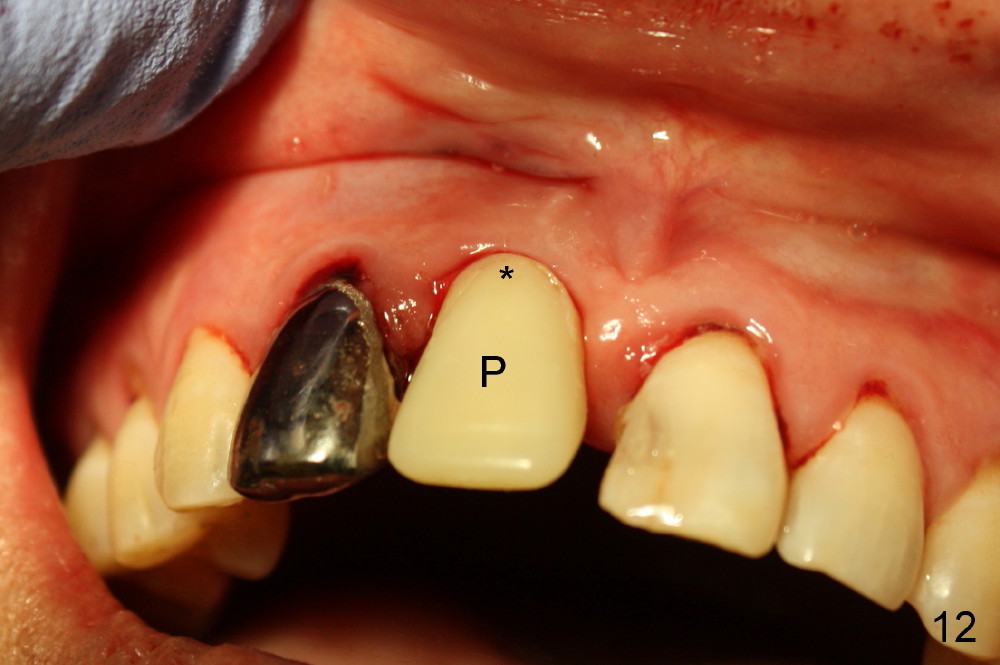

A 64-year-old lady requests replacing #7 and 8 crowns (Fig.1,2). When #8 is extracted, the labial plate is found to be missing (Fig.3). Following 2 mm pilot drill (Fig.4,5 P), 3.8 mm tap drill (Fig.6,7 T) and 4.5x14 mm implant (Fig.8 I) and 4.8 mm abutment (Fig.9 A), corticocancellous bone is harvested from the left tuberosity and placed in the labial gap of the socket (Fig.10 G). Collagen dressing is placed over the bone graft (Fig.11 C). The former is secured in place by an immediate provisional (P).

The patient returns for follow up 8 days postop and the labial margin of the provisional looks long. The metal crown is changed to a provisional at the visit. Eight days later, the provisional at the site of #8 is removed for labial margin trimming; the labial gingiva heals (Fig.14 *). The labial plate remains slightly convex (Fig.15). The labial margin of the provisional at the site of #8 is at the same level of that of #9.